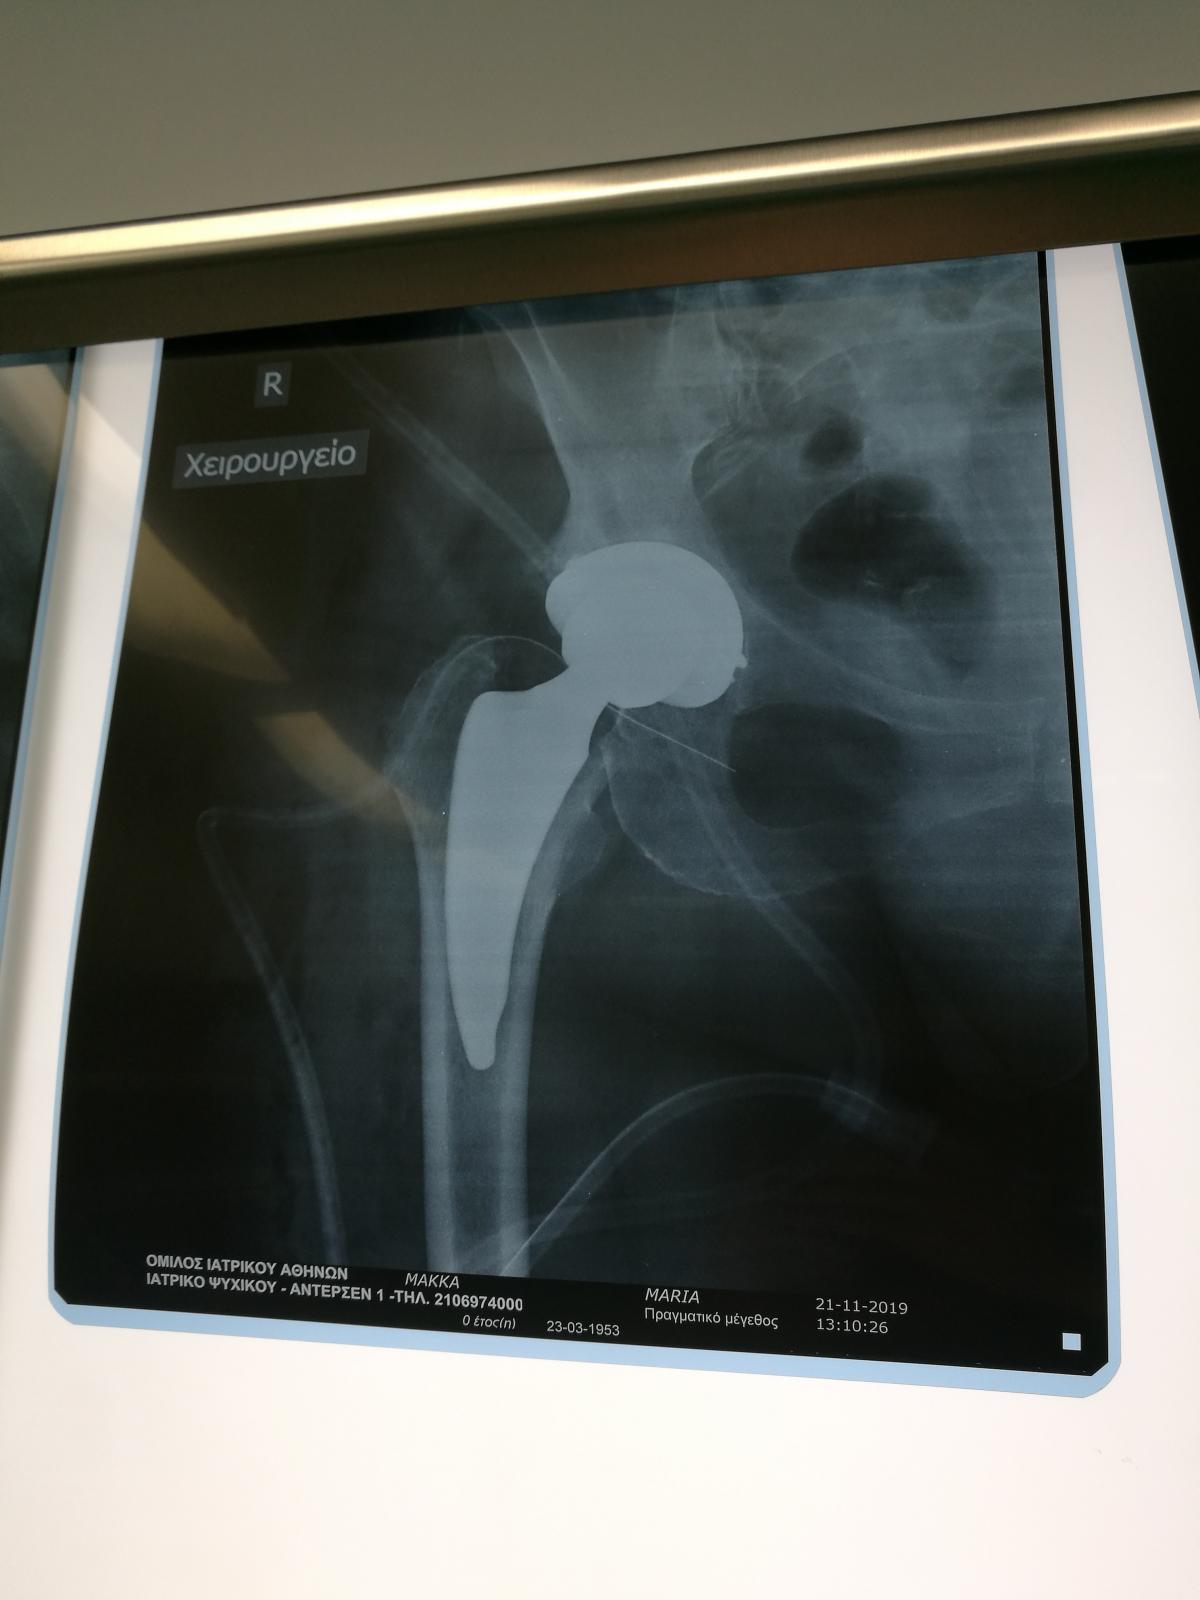

Компанія Lima надала стажування в ортопедичній приватній клініці місті Афіни Греція в листопаді 2019 року. Ендопротезування кульшового суглоба протезами компанії Lima малоінвазивним передньо-латеральний доступом у професора Христодулоса.